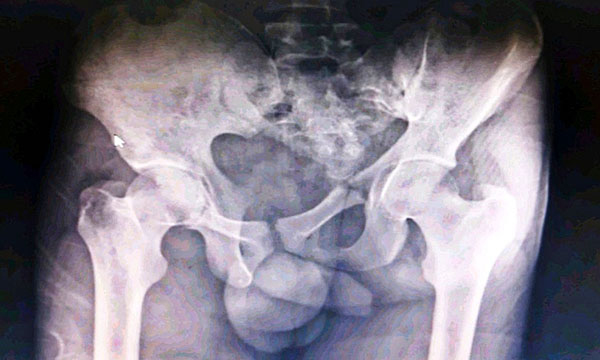

Managing pelvic fractures with haemorrhage using a multidisciplinary team approach: a case report from India

Pelvic fractures with haemorrhage are associated with high mortality and morbidity. This article describes the case of a 21-year-old man who was admitted to the emergency department of a hospital in India with a pelvic fracture and haemorrhage following a road traffic accident. It highlights the crucial role of nurses in coordinating the initial assessment, diagnostic investigations and treatment as well as the ongoing management of patients presenting with such injuries. Timely interventions by a multidisciplinary team are critical for preventing hypovolaemic shock, reducing mortality and limiting disability.